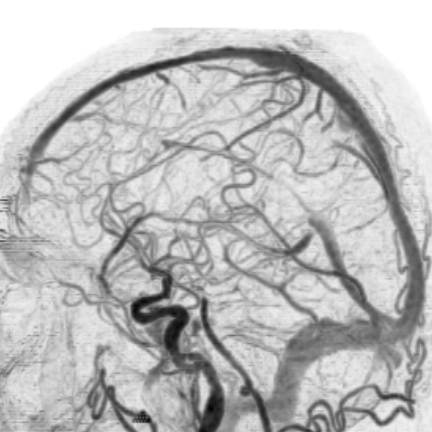

右侧MCA长节段血管变细狭长

长节段MCA血管狭长变细,尤以近端为重

乍一看血管似乎还可以